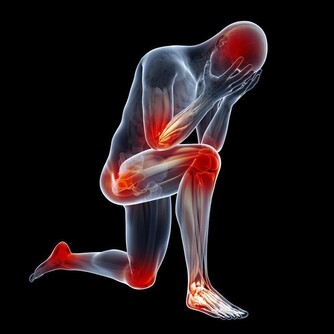

尾龍骨︰ 現在的人類,即使在沒有尾巴的情況下仍能好好平衡,因此不再需要尾巴。 男性乳突︰ 胎兒在首60天「還未定性」,因此是以同一模式發育,並長有乳突,但之後當它是一個男胎,代表男性的Y染色體產生作用後,胎兒的男性性器就繼續發育,胸部則停止發育。 智慧齒︰ 由於現代人類不用像原始人般咀嚼生的菜或肉,因此顎骨愈來愈小,因此不能容下智慧齒。 豎「雞皮」︰ 人類祖先有較多毛髮,因此當豎「雞皮」時,毛髮看起來更大,可以嚇退敵人。現在人類在受驚或寒冷時會豎「雞皮」,但作用已不如以前般大。 第三眼蓋︰ 近鼻子的眼角有一塊皮其實不用存在。雀鳥或爬蟲類仍保留該多出的半透明眼蓋,可一邊保護眼睛,一邊看東西。